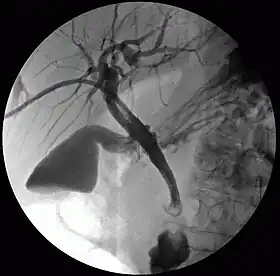

Cholangiography is the imaging of the bile duct (also known as the biliary tree) by x-rays and an injection of contrast medium.[1]

1. Percutaneous transhepatic cholangiography (PTC): Examination of liver and bile ducts by x-rays. This is accomplished by the insertion of a thin needle into the liver carrying a contrast medium to help to see blockage in liver and bile ducts.